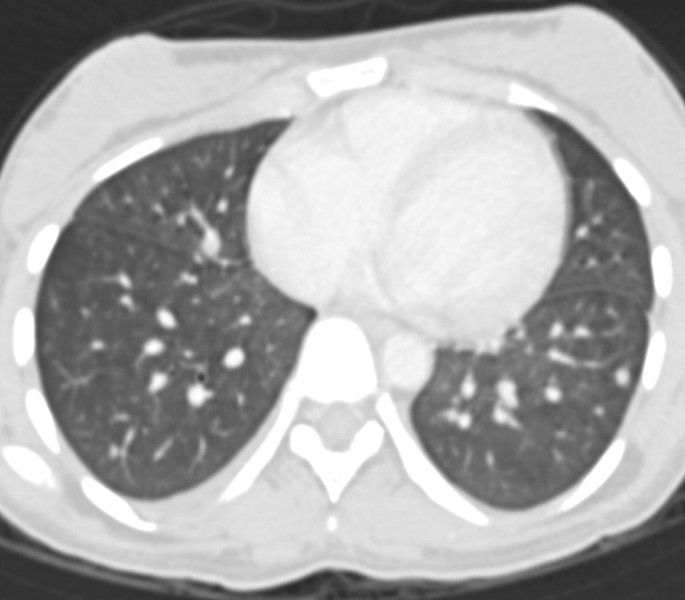

Without any further testing to avoid wasting valuable time, systemic steroid (dexamethasone 10 mg/m2) therapy was initiated. Appropriate respiratory care in the form of bilevel positive airway pressure (BiPAP) was given. A computed tomography (CT) scan of thorax showed multiple bilateral lung nodules with surrounding changes in ground-glass opacity predominantly in the lower lobes (Fig. 2).The differential diagnosis based on her imaging findings included infective causes (bacterial, viral, fungal), leukemic infiltrates, acute respiratory distress syndrome (ARDS), leukostasis as part of hyperleukocytosis, drug toxicity, pulmonary oedema and pulmonary haemorrhage. Leukostasis was ruled out since the patient had a low TLC (2.9 × 109/L), and a requirement for leukostasis is a very high WBC count (> 100 × 109/L). Further, radiological studies revealed lung nodules with patchy changes in ground-glass opacity whereas leukostasis is characterised by more confluent opacities with interlobular septal thickening.

a Axial computed tomography (CT) scan showing bilateral pulmonary parenchymal nodules and ground-glass changes in the middle lobe, lingular segment of left upper lobe and bilateral lower lobes. Upper lobes are less affected. b Coronal CT scan showing bilateral pulmonary parenchymal nodules and ground-glass changes in the middle lobe, lingular segment of left upper lobe and bilateral lower lobes. Upper lobes are less affected

Univariate analysis identified a high WBC count at presentation, with 5 × 109/L as the most significant cutoff point, as a prognostic factor for severe DS [6]. This needs to be noted since in our case the TLC was much lower (2.9 × 109/L). Other prognostic factors for severe DS are abnormal levels of serum creatinine; FLT3-Internal Tandem Duplications (ITD) mutations; microgranular French American British (FAB) subtype; short promyelocytic leukaemia-retinoic acid receptor alpha (PML-RARA) isoform; and male sex [6]. As already stated, there are no clinical signs or laboratory tests to diagnose DS, nor is there a radiological finding pathognomonic for DS. Radiological features may be explained by the proposed hypotheses of pathophysiology of the DS. Most of the patients with DS show cardiomegaly, widening of the vascular pedicle width, increased pulmonary blood volume, peribronchial cuff, ground-glass opacity, septal lines and pleural effusion: these findings are similar to those of congestive heart failure with pulmonary oedema, but they can also probably be produced by leukemic lung infiltration and endothelial leakage [7]. In mild DS, lesions are prevalent in the lower lobes, while in severe DS, the lesions are diffuse, with no difference between peripheral or central regions [7]. Davis et al. [8] reported CT findings in three patients with DS, consisting of peripheral nodules, reticular and ground-glass opacity and pleural effusions. The CT scan showed similar findings in our case. These authors also reported the case of a patient with DS who developed pneumothorax [8]. Other reported histological findings in analyses of lungs are extensive interstitial and alveolar lung infiltration by maturing myeloid cells, endothelial cell damage, oedema, haemorrhage and fibrinous exudates that correspond to poorly defined centrilobular nodules and ground-glass opacity with or without interlobular septal thickening [7].